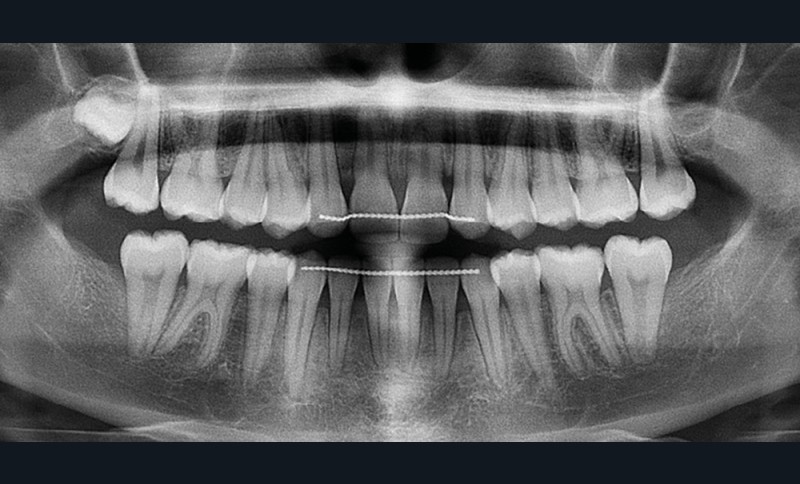

Les examens cliniques et radiologiques ont mis en évidence l’inclusion de 13 et 23, une légère classe II bilatérale par perte d’ancrage, un biotype parodontal de type IV de Maynard et Wilson avec une insertion du frein mandibulaire antérieur papillaire, une biproalvéolie et une typologie hypodivergente. La réalisation d’un examen tridimensionnel a permis de confirmer la localisation palatine de 23 et vestibulaire de 13 ainsi que de visualiser l’étendue des résorptions radiculaires touchant 12, 21 et 22 (fig. 1a-i).

Le plan de traitement choisi comprend les extractions de 63, 12, 22, 34 et 44. Ce choix s’est porté d’une part sur le fait de la présence de résorptions très avancées de 12 et 22 et d’autre part sur la correction de la biproalvéolie facilitée par l’extraction de 34 et 44 qui ont par ailleurs un diamètre légèrement inférieur à 35 et 45.

Les caches esthétiques ont été progressivement diminués jusqu’à leur suppression complète. Une fois l’alignement des canines obtenu, la prise en charge de 11 et 21 sur un NiTi .014 a débuté. Des forces très douces avec un contrôle radiologique tous les trois mois ont ensuite permis l’alignement et la fermeture des derniers espaces maxillaires. Une coronoplastie soustractive de 13 et 23 a été réalisée pour les transformer en 12 et 22. La vitalité de 11 et 21 a été conservée. En contention, deux fils collés ont été mis en place (13-23 et 33-43) ainsi qu’une gouttière thermoformée maxillaire amovible à port nocturne. Le traitement a duré vingt-neuf mois (fig. 5a-f).

Les résorptions radiculaires des dents adjacentes aux canines maxillaires incluses sont en effet fréquentes avec un risque plus important chez les femmes. La localisation sagittale de la canine incluse constitue un facteur de risque dans la présence de résorptions radiculaires [3]. Le recours aux examens tridimensionnels est donc indispensable dans le traitement de ces cas.